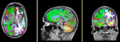

Single channel automatic segmentation of t1w-MRI brain scans into the major tissue classes (gray matter, white matter, csf). The task can only be applied to t1w brain scan showing parts of the skull and neck. The pipeline consist of the following steps:

| Template (T1) | CSF | GM | WM |

Result